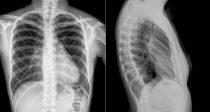

Согласно исследованию, опубликованному в журнале Chest , искусственный интеллект улучшает интерпретацию рентгеновских изображений грудной клетки практикующими врачами-нерентгенологами, что может быть полезно […]… далее